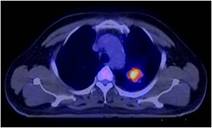

Cách thức điều trị: bệnh nhân được quyết định điều trị hóa chất phác đồ DC với liều Docetaxel (Taxotere) 75mg/m 2, truyền tĩnh mạch ngày 1, Carboplatin 300mg/m2, truyền tĩnh mạch ngày 1. Chu kỳ 3 tuần. Đánh giá sau 3 tuần. Bệnh nhân được điều trị hóa chất DC 3 chu kỳ. Đánh giá sau 3 tuần: Chụp PET/CT có đáp ứng tốt trên PET/CT.

Đáp ứng trên hình ảnh PET/CT như sau:

Khối u phổi trước điều trị: SUV=6,89 | Khối u phổi sau điều trị hóa chất 3 đợt: SUV=3,24 | Sau xạ trị và HC 6 đợt: khối u tan biến |